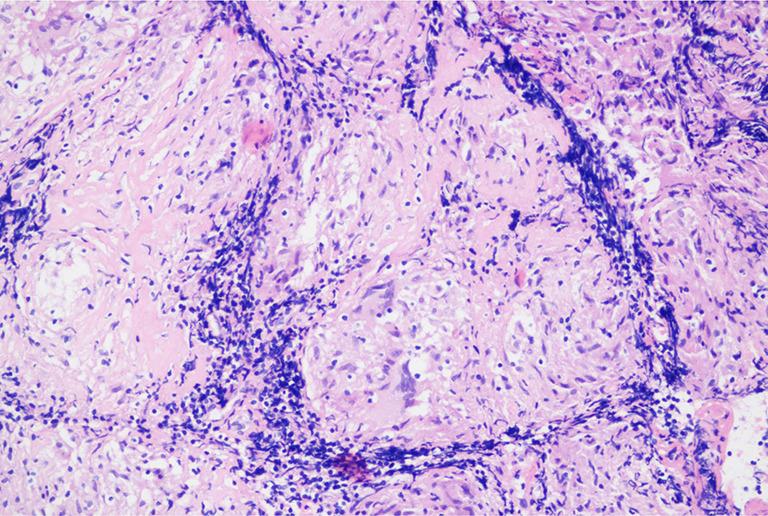

A 70-year-old man was hospitalized with cough and dyspnea for two months. After admission, through chest computed tomography (CT), ultrasound guided bilateral lung biopsy, left parietal pleural biopsy, and EBUS-CA-TBMCB, the final diagnosis was atypical sarcoidosis secondary FM. After taking glucocorticoid orally, the patient's condition improved significantly, and was discharged from the hospital. We continued following up outside the hospital, and the patient's condition was further improved.

The diagnosis of FM is mainly based on typical imaging manifestations. When the contrast-enhanced chest CT finds localized or diffuse soft tissue density shadows around the mediastinum and pulmonary hilum with an irregular shape, with or without calcification, particular attention should be paid to exclude FM. EBUS-CA-TBMCB, as an improved minimally invasive method, can obtain enough tissue samples for pathological diagnosis, which may be the effective biopsy method for the etiology of FM to avoid missed diagnosis and misdiagnosis in the future.

一名70岁男性因咳嗽、呼吸困难2个月入院。入院后,通过胸部计算机断层扫描(CT)、超声引导下双侧肺活检、左顶叶胸膜活检及EBUS-CA-TBMCB,最终诊断为非典型结节病继发FM。口服糖皮质激素后,患者病情明显改善,出院。我们继续在院外随访,患者病情进一步好转。

结论

FM的诊断主要基于典型的影像学表现。当胸部增强CT发现纵隔和肺门周围有局部或弥漫性软组织密度影,形态不规则,有无钙化时,应特别注意排除FM。EBUS-CA-TBMCB作为一种改良的微创方法,能够获取足够的组织样本进行病理诊断,可能是避免未来FM病因漏诊和误诊的有效活检方法。